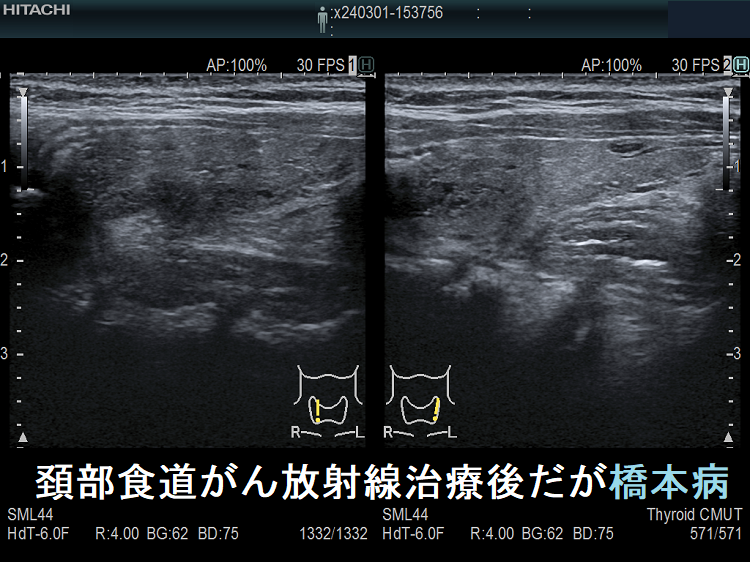

頚部食道がん放射線治療後だが橋本病